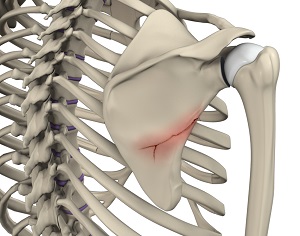

What is Fracture of the Shoulder Blade (Scapula)?

The scapula (shoulder blade) is a flat, triangular bone providing attachment to the muscles of the back, neck, chest, and arm. The scapula has a body, neck, and spine portion.

Scapular fractures are uncommon but do occur and require a large amount of force to fracture. They are usually the result of intense trauma, such as a high-speed motor vehicle accident or a fall from a height onto one’s back. They can also occur from a fall on an outstretched arm if the humeral head impacts the glenoid cavity.

Fractures of the scapula involving the neck or glenoid or with severe displacement have been associated with poor outcomes when treated non-operatively and would usually require surgical intervention to realign the bones properly and restore a functional, pain-free range of motion to the shoulder joint. Scapular fracture repair surgery has historically been performed through a large, open incision. Newer, minimally invasive techniques have evolved and surgery to repair scapular fractures can now be performed with arthroscopic techniques.